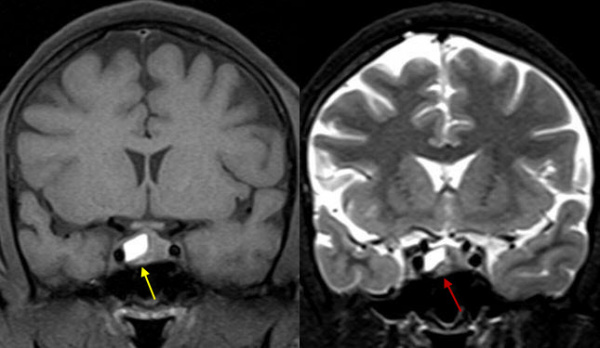

(Слева) МРТ, Т1 -ВИ, корональный срез: у женщины 32 лет с повышенным уровнем пролактина и галактореей визуализируется минимальное увеличение правых отделов гипофиза с легким истончением дна турецкого седла.

(Справа) МРТ, постконтрастное Т1-ВИ: у этой же пациентки в правых передних отделах гипофиза определяется объемное образование, которое накапливает контраст в меньшей степени, чем нормальная ткань гипофиза слева. Воронка имеет нормальное срединное расположение. Было проведено транссфеноидальное хирургическое удаление опухоли после выявления ее роста на фоне медикаментозной терапии. При резекции была выявлена пролактинома.